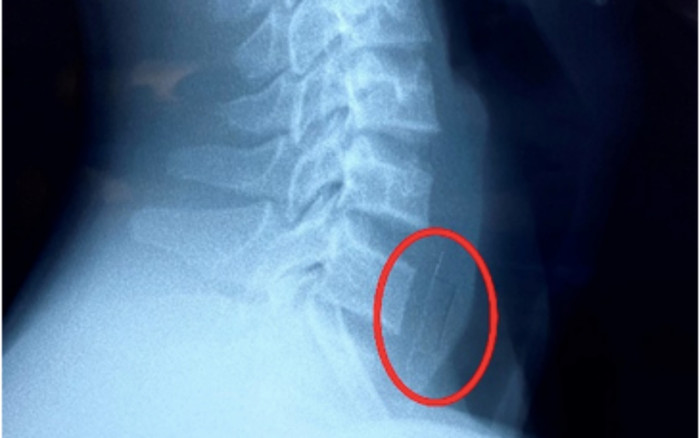

Hình ảnh XQuang dị vật cản quang ở thực quản. (Ảnh: BV Nhi đồng 1).

Sau đó bé đau nhiều khi nuốt, không ăn uống được, không khó thở. Khi đến khám tại bệnh viện địa phương, bé được chụp Xquang. Hình ảnh cho thấy nghi ngờ có dị vật cản quang vùng thực quản nên bé được chuyển đến BV Nhi Đồng 1.

Do vỏ viên thuốc to và sắc nhọn, nằm bên dưới miệng thực quản khoảng 2cm, nên quá trình tiến hành nội soi gặp nhiều khó khăn. Niêm mạc thực quản sau gắp dị vật trầy xước nhẹ. Bé hiện ổn và được tiếp tục theo dõi tại bệnh viện.